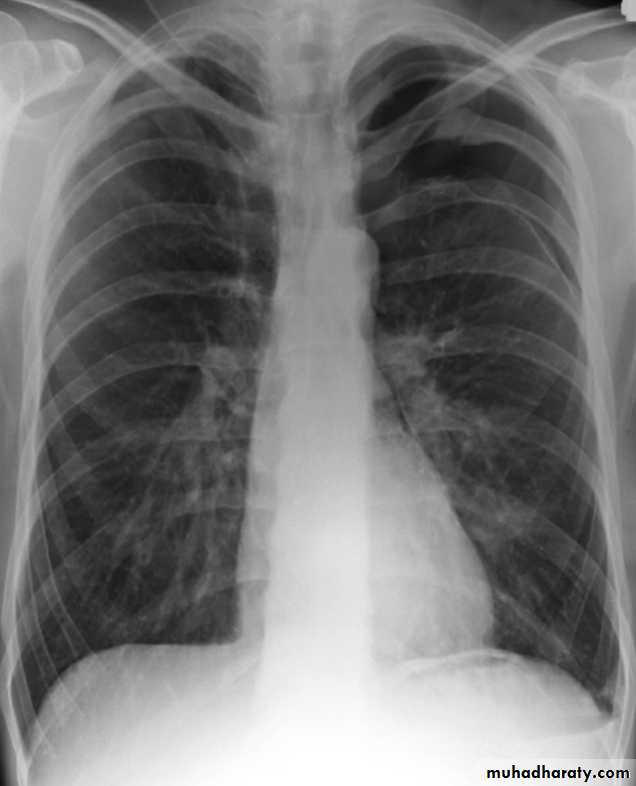

Pneumothorax

Pneumothorax refers to the presence of gas (air) in the pleural space. When this collection of gas is constantly enlarging with resulting compression of mediastinal structures it can be life-threatening and is known as a tension pneumothoraxIt is useful to divide pneumo thoraces into three categories :

Radiographic features

Chest radiograph

A pneumothorax is, when looked for, usually relatively easily appreciated. Typically they demonstrate:

visible visceral pleural edge see as a very thin, sharp white line

no lung markings are seen peripheral to this line

the peripheral space is radiolucent compared to adjacent lung

the lung may completely collapse

the mediastinum should not shift away from the pneumothorax unless a tension pneumothorax is present